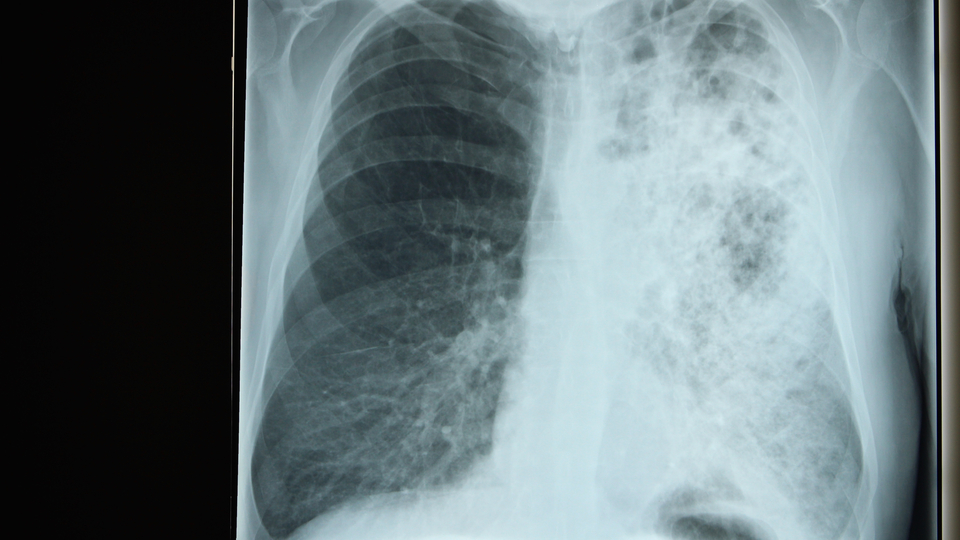

Dr. Öğr. Üy. Mikrobiyolog İpek Ada Alver, "Klima filtrelerinin tıkanması sonucu üreyen hastalık yapıcı mikroorganizmalar akciğerlere yerleşerek pnömoni (zatürree) benzeri hastalıklara sebep olduğundan koronavirüs çok daha ağır geçebilir" açıklamasında bulundu.

Lejyoner hastalığının şiddet aralığı, hafif bir öksürük ve düşük ateşten, hızlıca ilerleyen pnömoniye kadar gidebilmektedir. Özellikle, erkeklerde, 50 yaş üstü erişkinlerde, sigara kullananlarda, hasta, bağışıklık sistemi zayıflamış ve akciğer rahatsızlığı bulunan kişilerde daha fazla meydana gelmektedir" ifadelerini kullandı.

Lejyoner hastalığının pnömoninin akut tipi olup erken safhalarda ateş, baş ağrısı, kas ağrısı, ileri safhalarda ise nefes darlığı, ishal, bulantı, merkezi sinir sistemi bozukluklarına yol açabildiğini belirten İpek Ada Alver, "Bu hastalığa bağlı ölüm oranının yüzde 10-15 olduğu belirlenmiştir. Pontiak ateşi de soğuk algınlığına benzer semptomlar göstermektedir. İnkübasyon (kuluçka süresi) periyodu 1-3 gün süren hastalıkta yüksek ateş görülmekte ve 2-5 gün içerisinde iyileşme sağlanabilmektedir. Pontiak ateşinde, pnömoni oluşmadığı sürece ölüm görülmemektedir" diyerek klimalardan bulaşan bakterilerin sağlığı tehdit edici etkilerinden bahsetti.

Klimalardan bulaşan enfeksiyonların kaynağı olan bakterinin zatürreeye neden olduğunu belirten İpek Ada Alver, "Koronavirüs de ARDS (Akut Solunum Sıkıntısı Sendromu) tablosuna neden olduğundan ve solunumu önemli ölçüde etkilediğinden dolayı klimalardan bulaşan enfeksiyonların yol açtığı zatürree tablosu ile birleşince ölüm oranlarında artışları tetikleyebileceğinden klima bakımına önem verilmesi gerekmektedir" dedi.